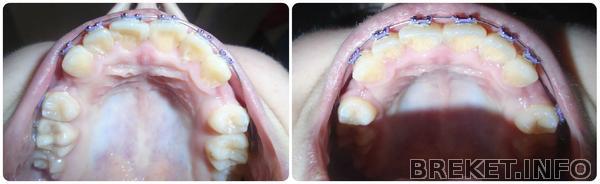

1.5 месяца

Вот уже и 1.5 месяца прошло.... Зубки двигаются медленно, но в верном направлении... Чему я конечно рада... Не по теме, но у меня очень сильно сохнут губы, ничего не помагает, может подскажите, чем вы пользовались)Ну а пока фотки для сравнения.... На первом коллаже разница 3 недели, на втором 2. А на последнем фото в один день только немного с разных ракурсов.

Изменения есть или мне кажется?